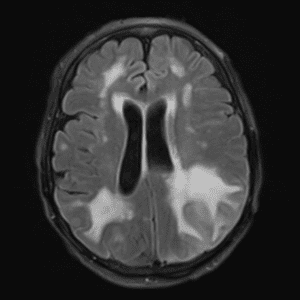

Case #14

CNS toxoplasmosis